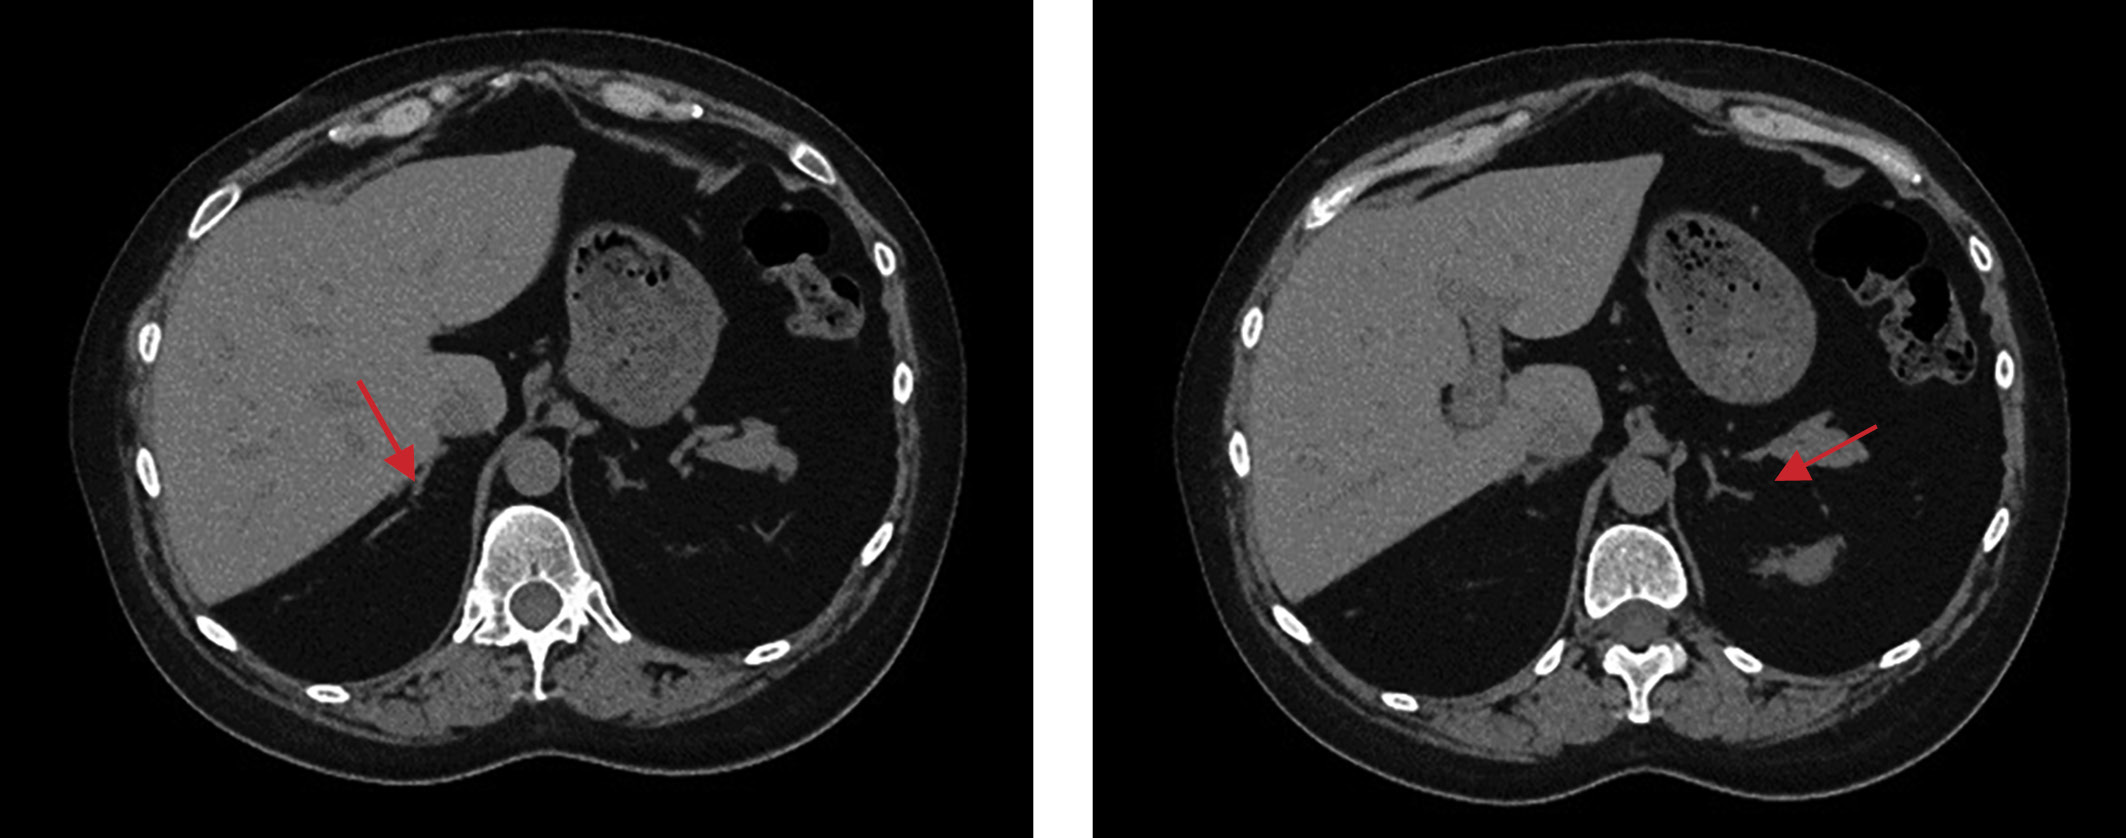

3. Рисунок 3. Мультиспиральная компьютерная томография надпочечников без контрастирования пациентки №2.

Посмотреть (202KB)